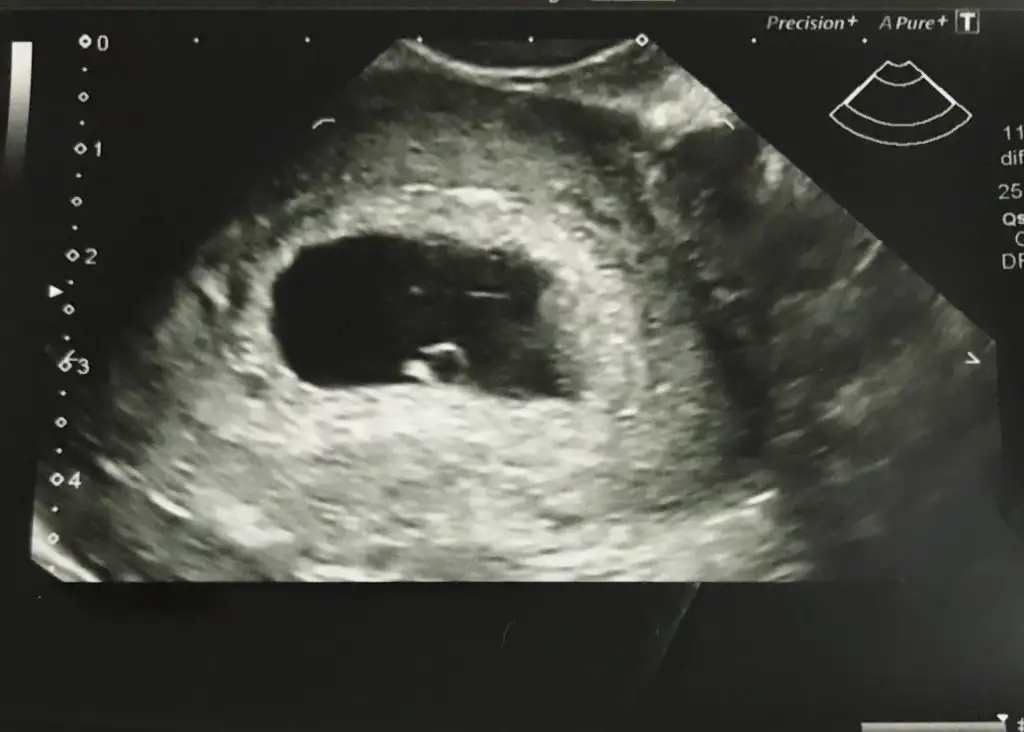

Ben kese konumunu pek tuttugunu sanmıyorum ben nub tahmini yapıyorum 11 yada 12 hafta olmalı kesede yolk saç nerde ise yani sag tarafta hafif kabarık beyaz parlak alan sagda tabi siz vajinal bakıldıgı için asıl solda olmuş oluyor karından bakılınca asıl sol olmuş olacaktı ve erkekAyy çok teşekkür ederim en azından fikir verdiniz bana sağlıkla gelsin inşallah :) peki neye göre sağda ve ya solda diyoruz onu da sorsam size sanırım anlıyorsunuz bu konudan :)

12 yada 13 hafta olunca paylaşın nub için yada 6 hafta 7 hafta keseEki Görüntüle 2597646 ondan önceki bu var canim

Nųb dediginiz tam olarak ne oluyo12 yada 13 hafta olunca paylaşın nub için yada 6 hafta 7 hafta kese

12 yada 13 hafta olunca paylaşın nub için yada 6 hafta 7 hafta kese

Bacak arası dik ise erkek paralel ise kız